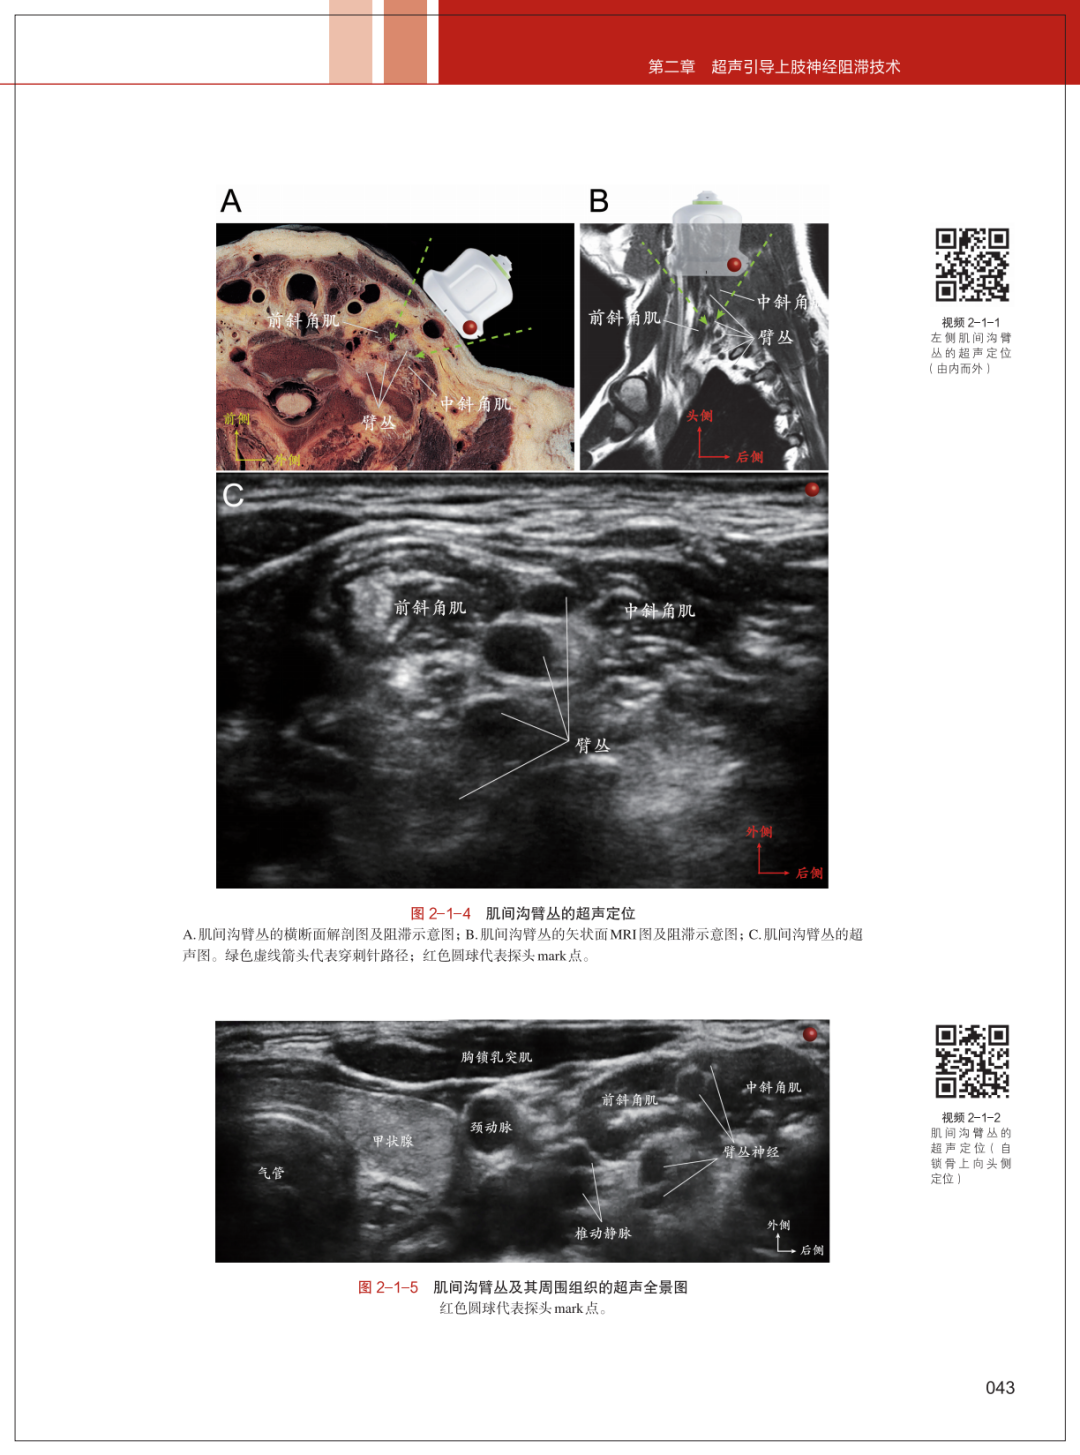

相较于第一版,新版亮点十足。全书共11章,以解剖为根基、问题为导向,系统覆盖头面部、脊柱、胸腹壁等全身各部位神经阻滞技术,新增自主神经阻滞章节,详解腹腔神经丛、交感神经节等复杂结构的超声引导方法,填补国内技术空白。创新采用解剖、影像、超声三维融合编写模式,搭配上千幅高清图示与600+高清操作视频,扫码即可实现“扫描即学、观看即练”。从基础原理、操作规范到并发症处理,从传统技术到新型局麻药应用、未来发展方向,满足临床实战与知识更新需求。

本书的核心价值在于其“以解剖为基础,以问题为导向”的编写理念。第二版延续了首版图文并茂的特点,结合高清超声图像、MRI解剖示意图及临床病例,详细解析了头面部、脊柱、胸腹壁、四肢等全身各部位的神经阻滞技术。